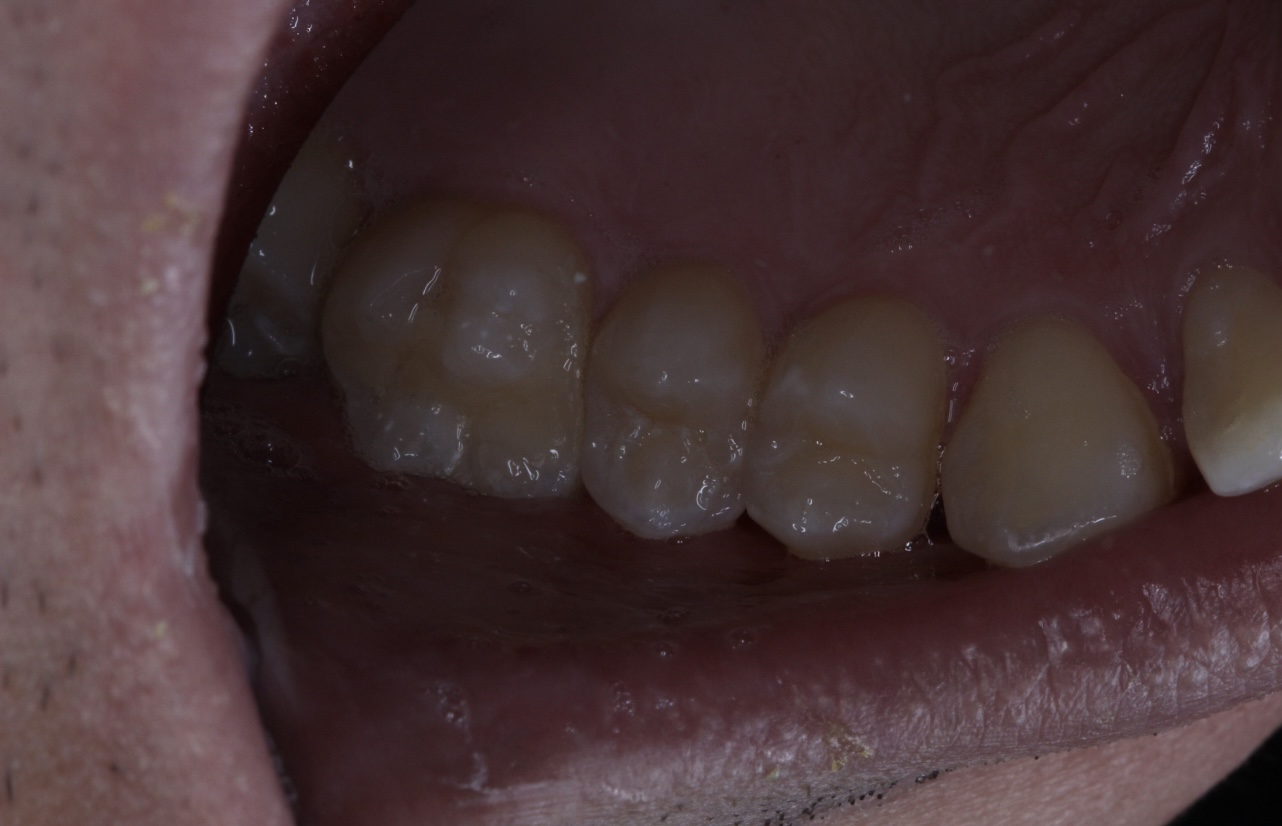

Ещё первый сказал, что у меня только 26 и 27 с кариозной полостью. А второй сказал, что только 16 и 17.

Оба ебланы?